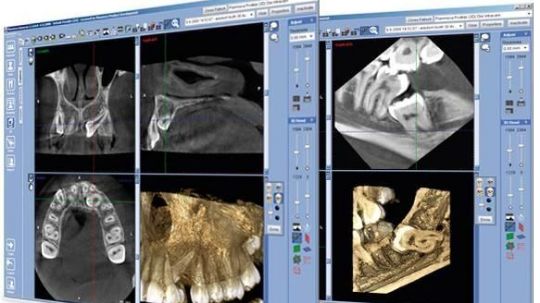

Один из самых информативных рентгеновских способов качественной диагностики заболеваний челюстно-лицевого аппарата. В результате КЛКТ врач получает 3D изображение исследуемого участка. Использование КЛКТ в стоматологии, лицевой хирургии позволяет обнаружить отклонения, поставить точный диагноз и назначить необходимое лечение

Пациент занимает сидячее положение, на него надевается защитный фартук. После настройки конусно-лучевого томографа в течение 20-30 секунд производится непосредственно сканирование. Датчик вращается с высокой скоростью и передает информацию на компьютер. Полученные данные с помощью специальной программы записываются на магнитный носитель и в дальнейшем анализируются рентгенологом и лечащим врачом, запись сохраняется и может быть использована для сравнительного диагностирования в дальнейшем лечении.

Для формирования качественного снимка КЛКТ во время процедуры должна соблюдаться неподвижность. Глотательные и жевательные движения могут привести к искажению изображения и необходимости повторения КЛКТ.